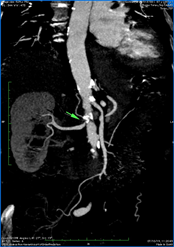

Blood tests revealed no changes, except an Erythrocyte sedimentation rate (ESR) of 56m, and C-reactive protein (CRP) of 44 mg/L. Plasma and urinary catecholamine levels were within the reference values. The autoimmunity study was negative. The electrocardiogram showed sinus rhythm, with a heart rate of 73 beats per minute, with no changes in rhythm, conduction, or ventricular repolarization. The 24-hour Holter confirmed the baseline sinus rhythm and some periods of 2nd-degree atrioventricular block Mobitz I during sleep. To complete de cardiac study, an echocardiogram was performed, which revealed mild mitral-aortic degenerative changes, aortic valve fibrosis, mitral ring calcification, mild regurgitation, and an enlarged left atrium. For the absence of palpable pulses, an Arterial Eco-Doppler of the Upper Limbs was performed, revealing a significant stenosis of the axillary arteries bilaterally, more severe on the right and with distal hemodynamic compromise. To exclude a Giant Cell Arteritis a Cerebral Vessel Wall MRI was performed and excluded changes in the temporal artery. Lastly, the Thoracic and Abdominal Angio-CT showed a diffuse thickening of the aorta wall, (Figure 1), stenosis of the left subclavian artery (Figure 2 & 3) with an inflammatory component, reduction in the caliber of the right subclavian artery and severe stenosis of the renal artery (Figure 4), thus suggesting a Takayasu Disease.

Figure 3 On coronal Angio-CT slice, stenosis of the left subclavian artery with an inflammatory component is indicated by a green arrow.

Figure 4 On coronal Angio-CT slice, severe stenosis of the right renal artery is indicated by a green arrow.